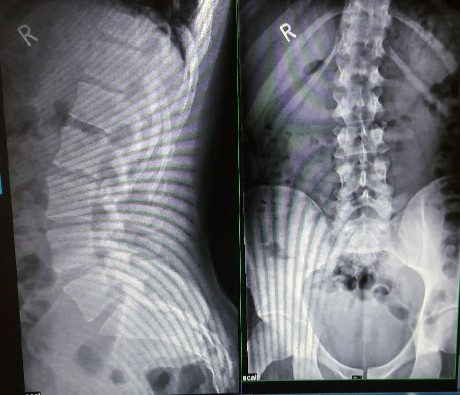

Entscheidend ist das Ergebnis und nach dem Foto und den Röntgenbildern zu urteilen, geht es hier um einen Rundrücken (Hyperkyphose), ein Hohlkreuz (Hyperlordose) sowie eine geringe begleitende Skoliose, was insbesondere bei einem Mann eine ganz typische Situation sein kann.

Insofern ist die Diagnose "leichter Scheuemann" keine vernünftige Diagnose! Anhand von Röntgenaufnahmen der gesamten Wirbelsäule sollten die entsprechenden Winkel ausgemessen werden.